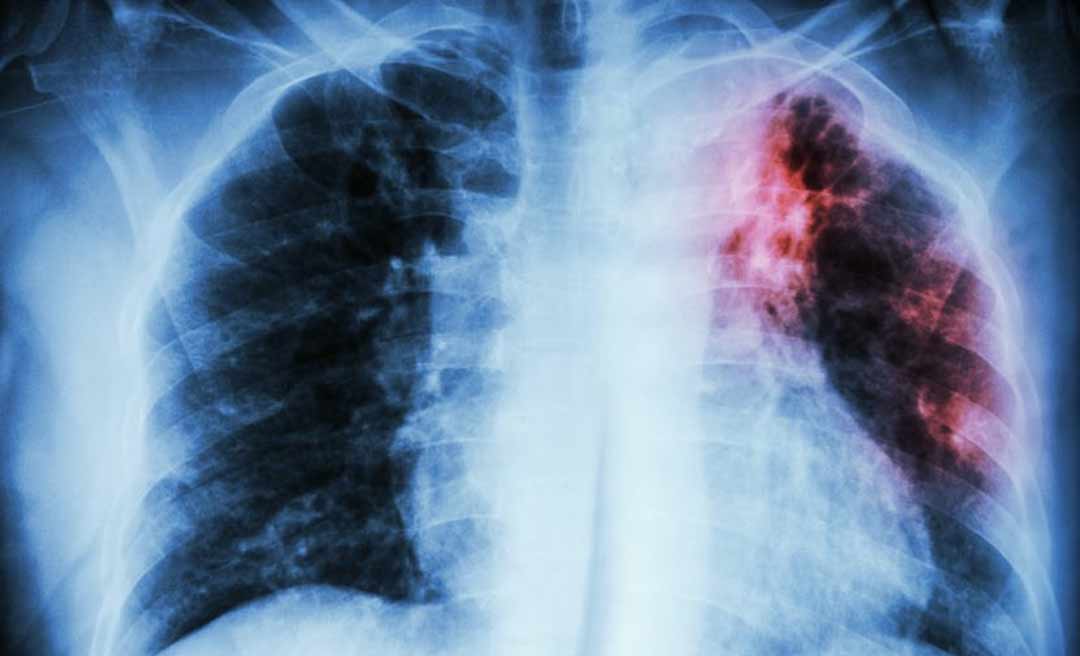

Um novo surto de doença respiratória, potencialmente mais letal que a covid-19, pode estar começando na Ásia. A embaixada chinesa no Cazaquistão alertou ontem seus cidadãos no país sobre uma nova “pneumonia desconhecida”. Segundo a China, no primeiro semestre deste ano 1.772 pessoas morreram da doença este ano, 628 delas apenas em junho. Cerca de 100.000 pessoas já teriam sido contaminadas.

“Essa taxa de mortalidade da doença é muito maior que a da covid-19 e as autoridades do Cazaquistão estão conduzindo um estudo comparativo do vírus sobre o qual ainda não há definição”, afirmou a embaixada chinesa, segundo o jornal South China Morning Post.

A Organização Mundial da Saúde afirmou ao diário chinês que tem conhecimento apenas da circulação da covid-19 no Cazaquistão, e que a doença causada pelo novo coronavírus pode explicar o aumento nos casos de pneumonia no país.